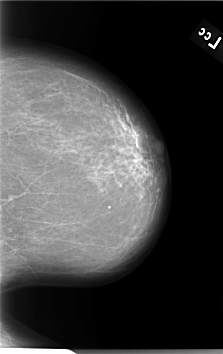

B_3060_1.LEFT_CC

LEFT_CC LINES 5664 PIXELS_PER_LINE 3568 BITS_PER_PIXEL 12 RESOLUTION 50 NON_OVERLAY